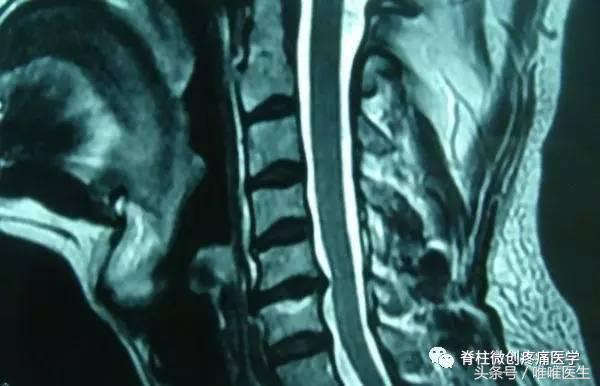

4.颈椎MRI检查

颈椎的MRI检查主要用于诊断颈椎间盘突出(目前,MRI成像技术是对椎间盘病变进行检查的最有效的方法。因为MRI成像对组织密度的分辨率高。无需作其他的创伤性检查,即能分辨正常纤维环与髓核。

并显示椎间盘突出的方向与程度,了解椎间盘有无变性,在这方面其优于CT。),观察颈椎后纵韧带钙化症,排除脊髓肿瘤及脊椎肿瘤,明确颈椎外伤和感染的病变程度。同样,MRI也是诊断椎体、椎间隙感染最有效、最特异的检查方法。